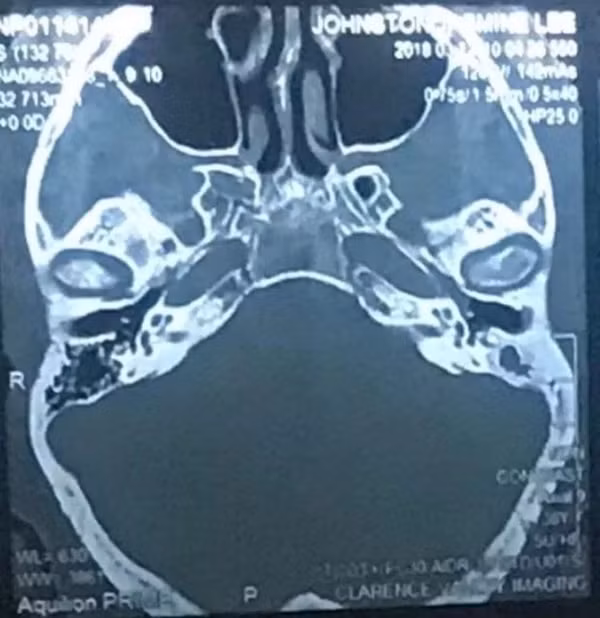

Khi đi khám, bác sĩ chỉ định cho cô uống thuốc kháng sinh, nhưng do không hiệu quả nên cuối cùng cô được chuyển đến gặp chuyên gia tai mũi họng để tiến hành chụp CT.

Tại đây, bác sĩ đã phát hiện ra bệnh nhiễm trùng sâu bên trong tai cô, đáng lo ngại hơn, ổ nhiễm trùng này còn cực kì gần với não và nguyên nhân gây ra nó là do một sợi bông mỏng rơi ra từ bông ngoái tai.